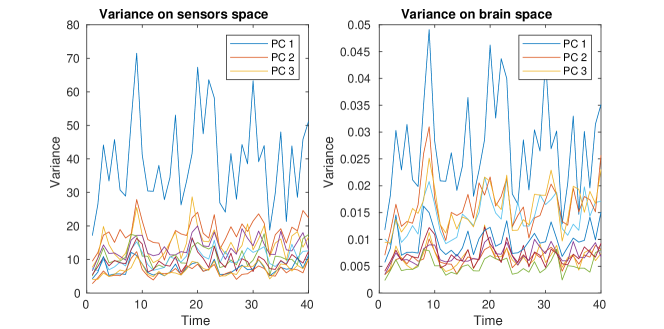

A regularization parameter common to all the PC components is chosen by inspecting the plot of the regularity of the first PC covariance functions () versus the residual norm, for different choices of the parameter. This is a version of the L-curve plot (Hansen, 2000) and is shown on the left panel of Figure B.2. Here we show the results for , in the appendices we show the results for . The energy maps of the estimated , and resulting from the analysis are shown in Figure 11. These are associated with the first three PC covariance functions , and . High intensity areas, in yellow, indicate which areas present high average interconnectivity, either by means of positive or negative correlation in time.

In Figure 12, we show the plot of variances associated with each time segment, describing the variation in time of the PC covariance functions, hence the variation in interconnectivity. The variance can be either defined on the sensors space, by normalizing the PC covariance functions , with the forward operator, or on the brain space, by normalizing the PC covariance functions on the brain space . Due to the presence of invisible dipoles, which are dipoles that display zero magnetic field on the sensors space, the two norms can be quite different, leading to different average variances for each PC covariance function. Due to the high sensitivity of the source space variances on the choice of the regularization parameter, we focus on the estimated variances on the sensors space.

The second part of the analysis focuses on applying the proposed methodology to a multi-subject setting. Specifically, different subjects are considered. For each subject, the 6 minutes scan is used to compute a covariance matrix, resulting in covariance matrices . The template geometry in Figure 10 is used as a model of the brain space. Algorithm 2 is then applied to find the PC covariance functions on the template brain, associated with . We run the algorithm for iterations, and choose the regularizing parameter to be by inspecting the L-curve plot in the right panel of Figure B.2. The results for are shown in the appendices. The energy maps of the estimated functions , and and the associated first three covariance functions , and , are shown in Figure 13. High intensity areas, in yellow, indicate which areas present high average connectivity. In Figure 14, we show the subject-specific associated variances, both in the sensors space and the brain space.

The presented methodology opens up the possibility to understand population level variation in functional connectivity, and indeed, whether, just as we need different forward operators for individuals (due to anatomical differences), we should also be considering both population and subject-specific connectivity maps when analyzing connectivity networks. In fact, it is of interest to note that in both the single and multi-subject settings, the areas with high interconnectivity, displayed in yellow in Figure 11 and 13, seem to be at least partially overlapping with the brain’s default network (Buckner et al., 2008; Yeo et al., 2011). The brain’s default network consists of the brain regions known to have highly correlated hemodynamic activity (i.e. highest functional connectivity levels), and to be most active, when the subject is not performing any specific task. An image of the spatial configuration of the default network can be found, for instance, in Figure 2 of Buckner et al. (2008). From the plots of the associated variances in the sensors space (left panel of Figure 12 and Figure 14) we can see that these areas are also the ones that show high variability in connectivity across time or across subjects. This might suggest that the brain’s default network is also the brain region that shows among the highest levels of spontaneous variability in connectivity.

The plots of the variances on the brain space (right panel of Figure 14), when compared to those on the sensors space (left panel of Figure 14), demonstrate that these type of studies are highly sensitive to the choice of the regularization, not only in terms of spatial configuration of the results, but also in terms of estimated variances on the brain space. With a naive ‘first reconstruct and then analyze’ approach, where the reconstructed data on the brain space replace those observed on the sensors space, this issue could go unnoticed, as the variability that does not fit the chosen model is implicitly discarded in the reconstruction step and does not appear in the subsequent analysis. Also, importantly, our analysis deals with statistical samples that are entire covariances, overcoming the limitations of seed-based approaches, where prior spatial information is required to choose the seed. Seed locations are usually informed by fMRI studies and this comes with the risk of biasing the analysis when comparing electrophysiological networks (MEG) and hemodynamic networks (fMRI).